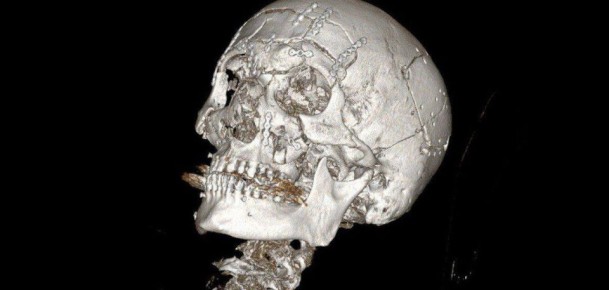

По версии следствия, 54-летний обвиняемый, являясь на момент совершения преступления лидером ОПГ в Самарской области, дал указание группе лиц за денежное вознаграждение совершить убийство начальника Тамбовского РОВД Валерия Джураева, ранее возглавлявшего подразделение по борьбе с организованной преступностью. Сотрудник правоохранительных органов был убит 13 апреля 2000 года на выходе из здания областной больницы на улице Московской в Тамбове.